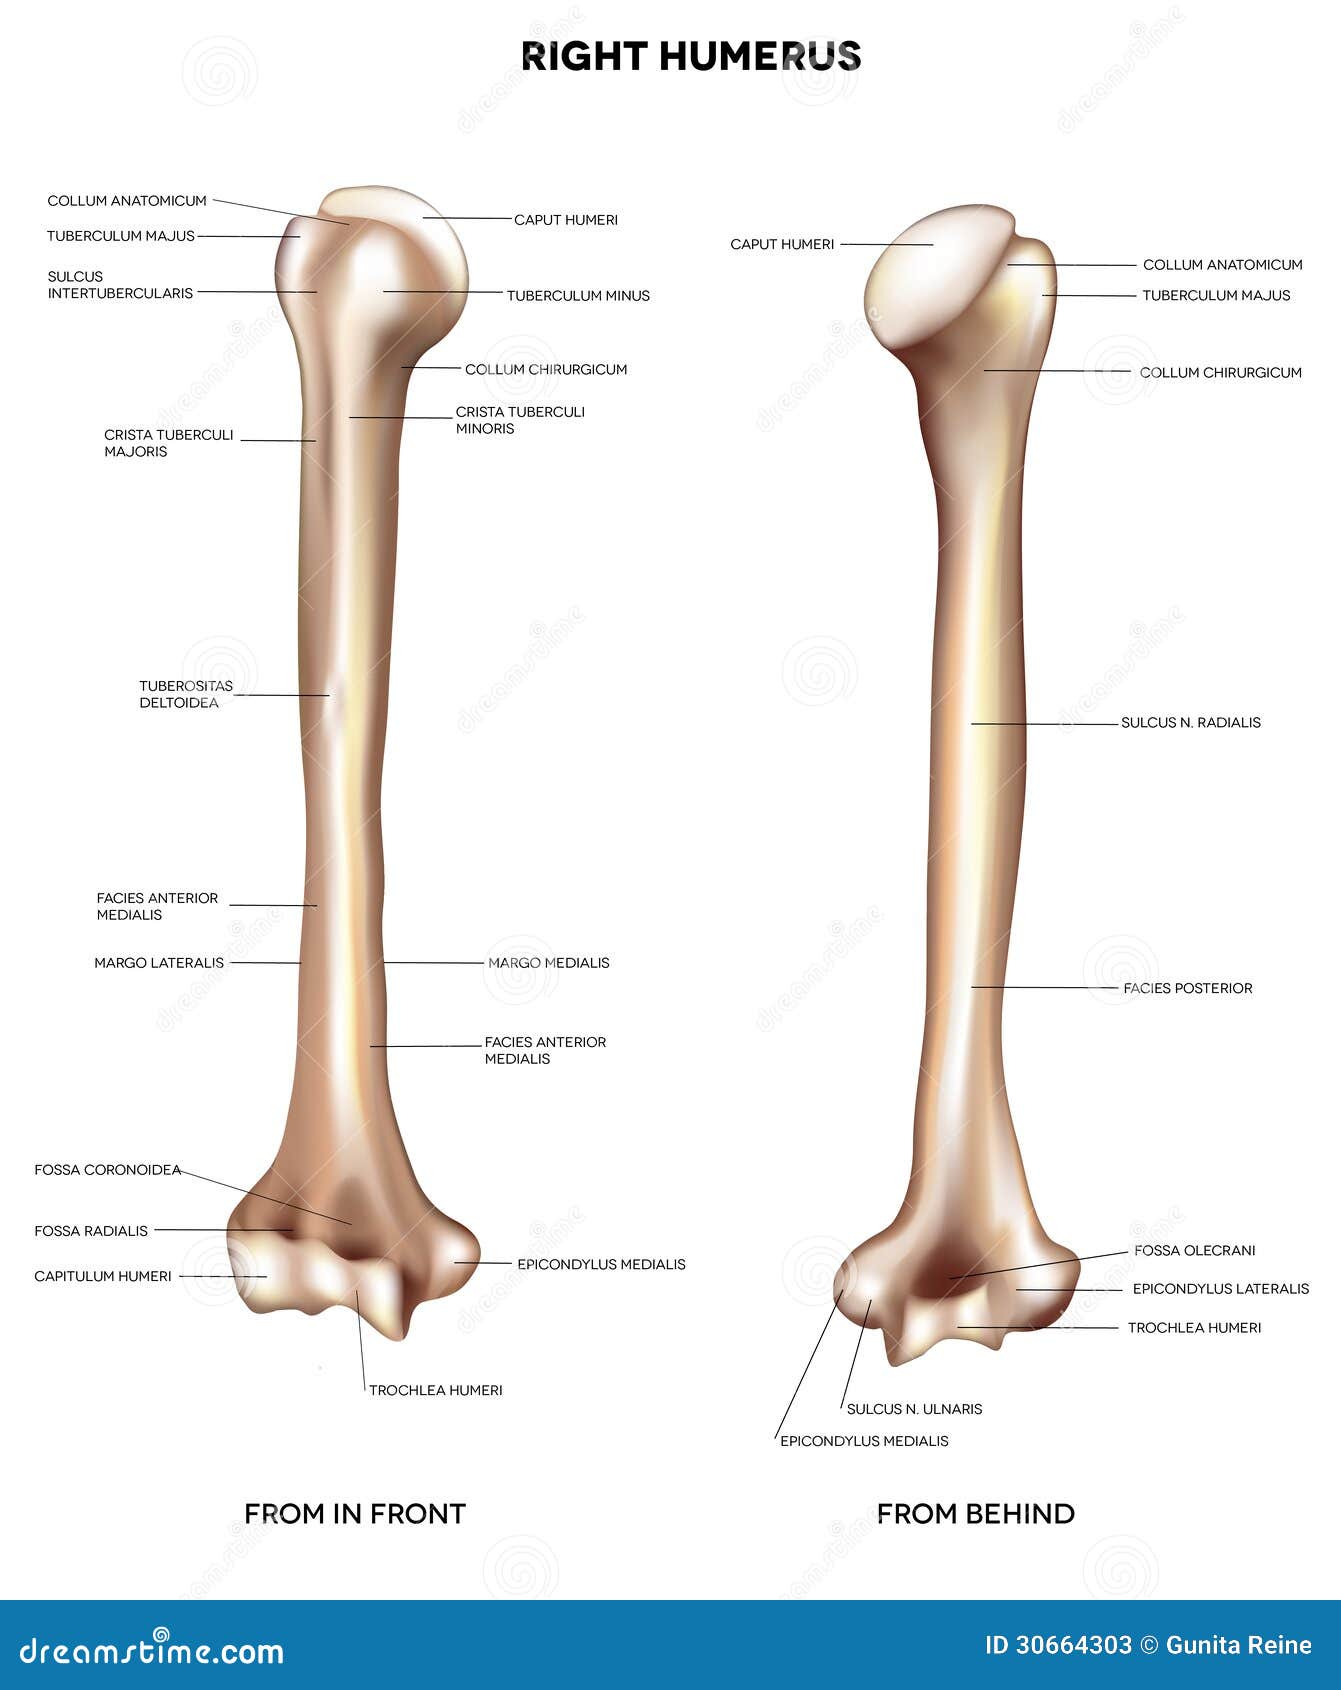

From fr.dreamstime.com

Anatomie D'humérus/bras Os D'anatomie Illustration Stock Humerus Bras De Fer La fracture du bras de fer, et du nerf radial. Find out how a splint,. The neer system divides the proximal humerus into four parts and considers not the fracture line, but the displacement as. Learn about the causes, treatment, and recovery of a humeral shaft fracture, a break in the middle part of the humerus bone. L’humérus est un. Humerus Bras De Fer.